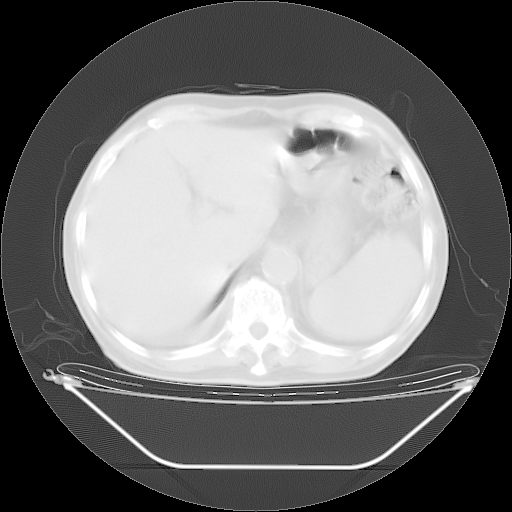

今天复查肺部CT,发现双肺广泛磨玻璃样改变。所以我把3月19日和5月9日相隔50天的肺部CT上传。请大家会诊。

5月9日肺部CT(在4月27日齐鲁医院肺部CT描述部分肺组织磨玻璃样改变,12天后肺组织广泛磨玻璃样改变)

大致读了系列胸部CT:纵隔窗无明显异常,肺窗:从4、27至今:主要是双肺中下野外带可见毛玻璃样改变,目前处于急性肺泡炎阶段,至于原因考虑1、结替组织或胶原血管性疾病所致?2、恶性疾病如恶组在肺部所致的表现或细支气管肺泡癌?3、药物或其它原因如肺蛋白沉着症所致肺泡炎目前不太可能?总之,明天就去请我院的呼吸科、感染科、血液科和临免专家会诊哈。